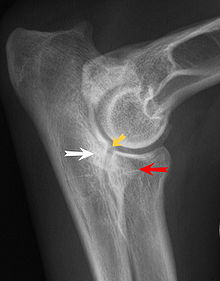

Fragmentation of the medial coronoid process

Most primary lesions are related to osteochondrosis, a disease of the joint cartilage, and osteochondritis dissecans (OCD), the separation of a flap of cartilage on the joint surface. Other common causes of elbow dysplasia include an ununited anconeal process (UAP) and fragmented or ununited medial coronoid process (FCP or FMCP).[1]

UAP is caused by a separation from the ulna of the ossification center of the anconeal process.[7] FMCP is caused by a failure of the coronoid process to unite with the ulna.